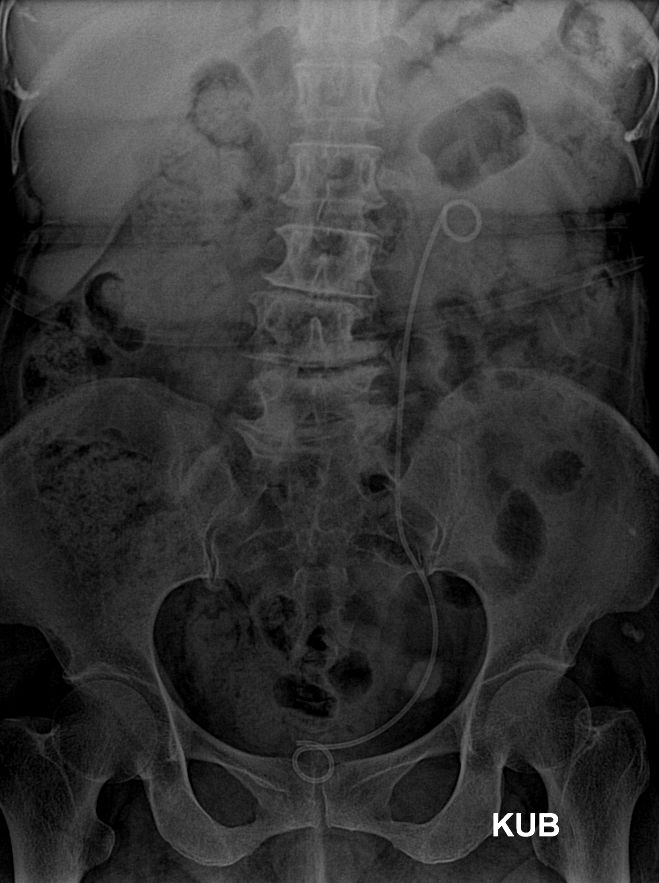

< X- ray 에서 보이는 D-J Stent 이미지>

위에 사진과 같이 요관부목(D-J Stent)를 삽입(설치)한다.

D-J Stnet는 신장(Kidney) 에서 방광(bladder)까지 연결된 긴 형태의 고무 막대로, 양측 끝이 말려져 있는 모양을 가지고 있다. D-J Stent의 초기 목적인 종양에 의해 발생한 폐색으로부터 요 배출을 돕는 것으로 출발하였으나, 최근에는 요로결석 수술 및 체외 충격파 시술 전 후, 요로결석으로 인한 폐색을 호전시킬 목적, 요관손상의 치료 및 요관의 누공의 치료 목적 등으로 그 목적이 더욱 확대되고 있다.

요관 부목을 삽입(설치)한 경우 한쪽 끝이 위에 사진과 같이 방광쪽으로 나와 있기 때문에 지속적으로 방광이 자극되어, 소변마려운 느낌이 든다. 이에 따라 소변을 자주 볼수 있으며, 옆구리 쪽(Stent를 삽입한 쪽)의 통증이나, 불편감을 호소하기도 한다. 요관부목(Stent)의 자극으로 인하여, 소변에 피(혈뇨)도 나올 수 있으나, 선지와같이 새빨간 피가 아니라면 물을 많이 마시면서 지켜볼 수는 있다. 삽입 후 수 시간 내지 1~3일 정도 후에는 안정되어 혈뇨도 대부분 사라진다.